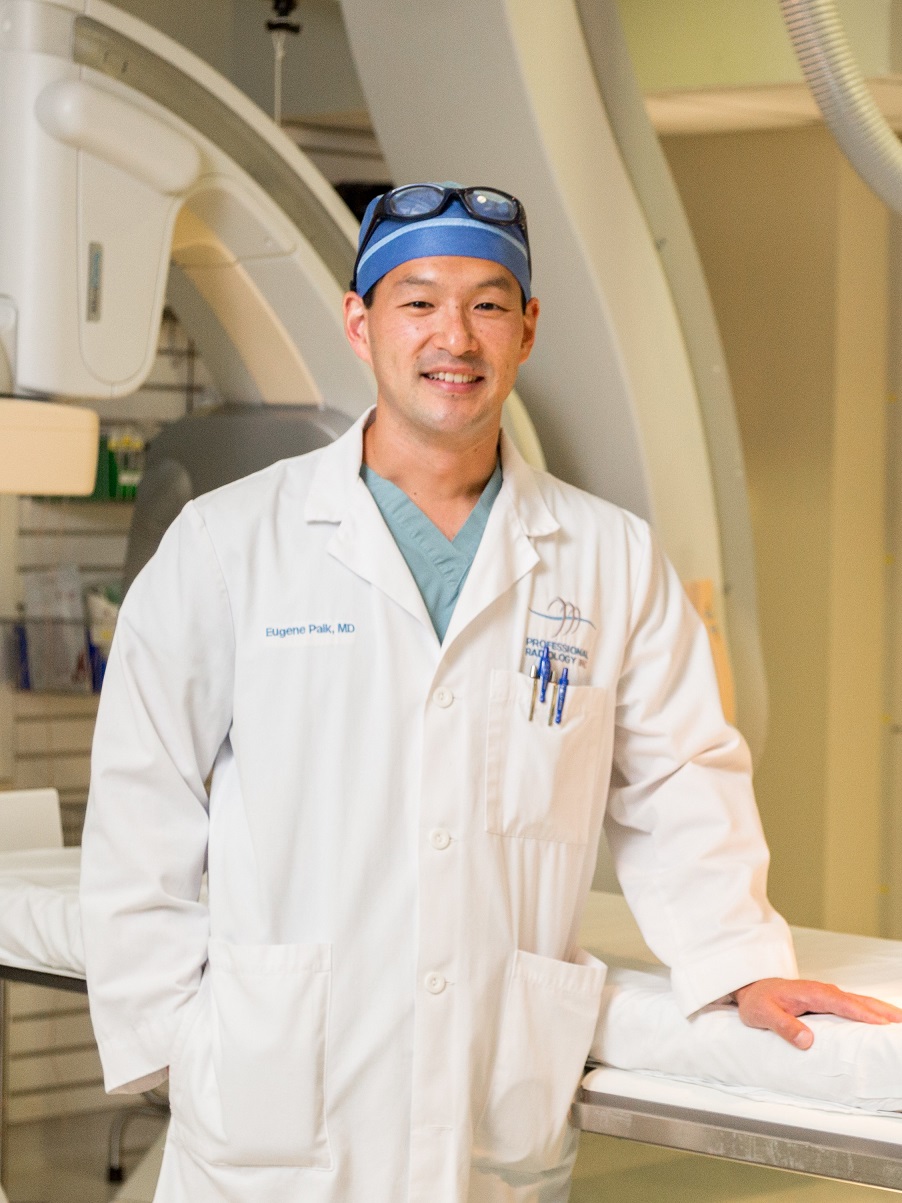

What is an Interventional Radiologist?

An interventional radiologist is a medical doctor who performs minimally invasive, targeted treatments using imaging guidance. Interventional radiologists are board certified radiologists that are fellowship trained in interventional treatments using guided imaging. Their specialized training is certified by the American Board of Medical Specialties.

An interventional radiologist is a medical doctor who performs minimally invasive, targeted treatments using imaging guidance. Interventional radiologists are board certified radiologists that are fellowship trained in interventional treatments using guided imaging. Their specialized training is certified by the American Board of Medical Specialties.